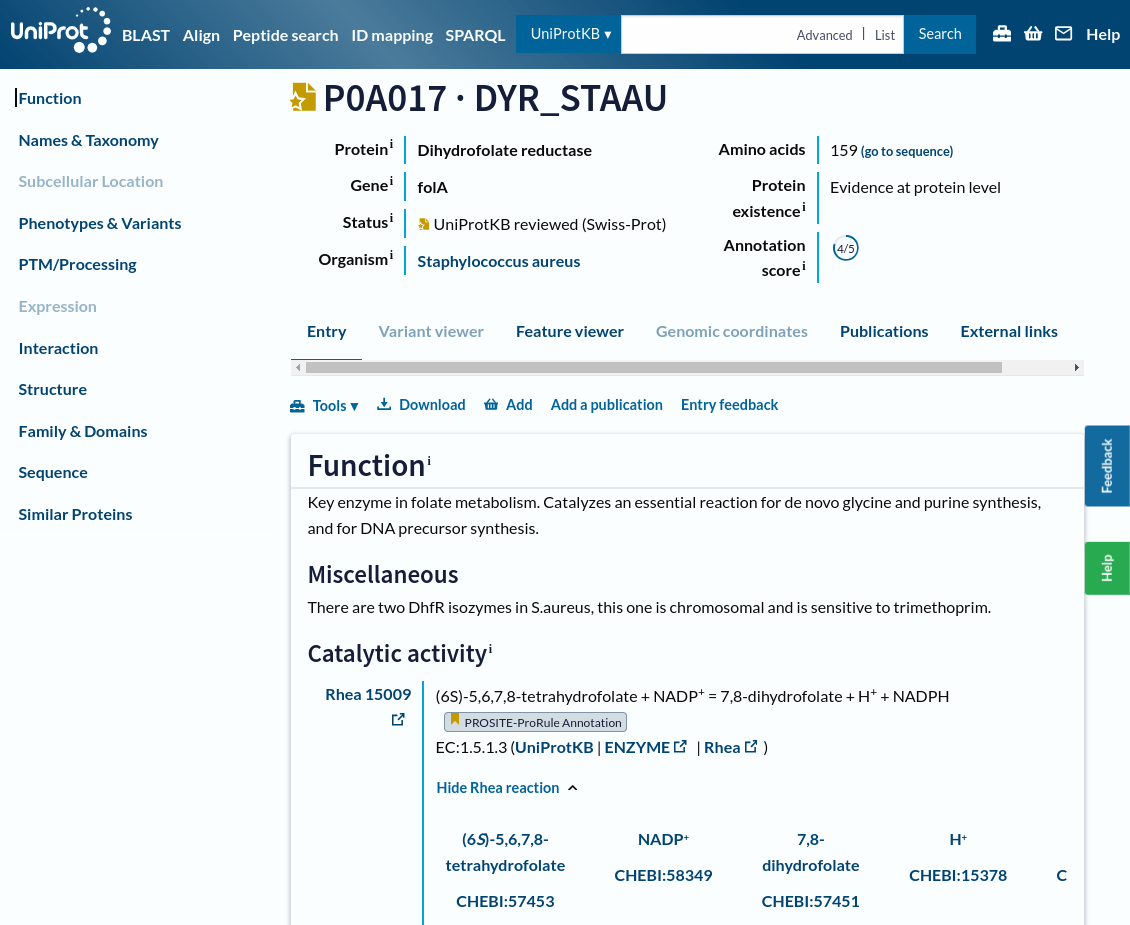

UniProt is a protein information database

Let's find information about our project's drug target: Dihydrofolate reductase

UniProt is a comprehensive database to access curated data about protein structures, functions, sequences, and annotations.

This page shows the results of a search in UniProtKB for a specific protein, in this case, "Dihydrofolate reductase"

On the left side, you have multiple filters to narrow your search results:

-

Reviewed (Swiss-Prot): Experts manually curated and verified these entries, ensuring high accuracy

-

Unreviewed (TrEMBL): These entries are automatically generated and have not been manually reviewed

Each row in the table represents a different protein entry

Entry ID: A unique identifier for the protein (e.g., P00383). You can click on this ID for detailed information about the protein

Protein Data Bank contains structures